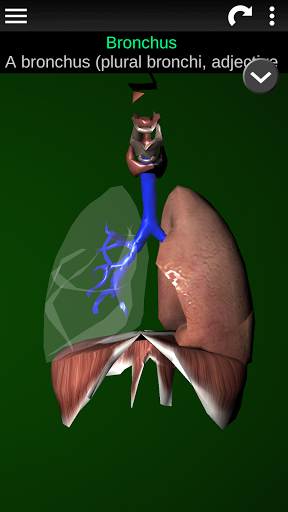

* Sistem pernafasan, yang meliputi trakea, bronkus, paru-paru dan animasi sistem ini.